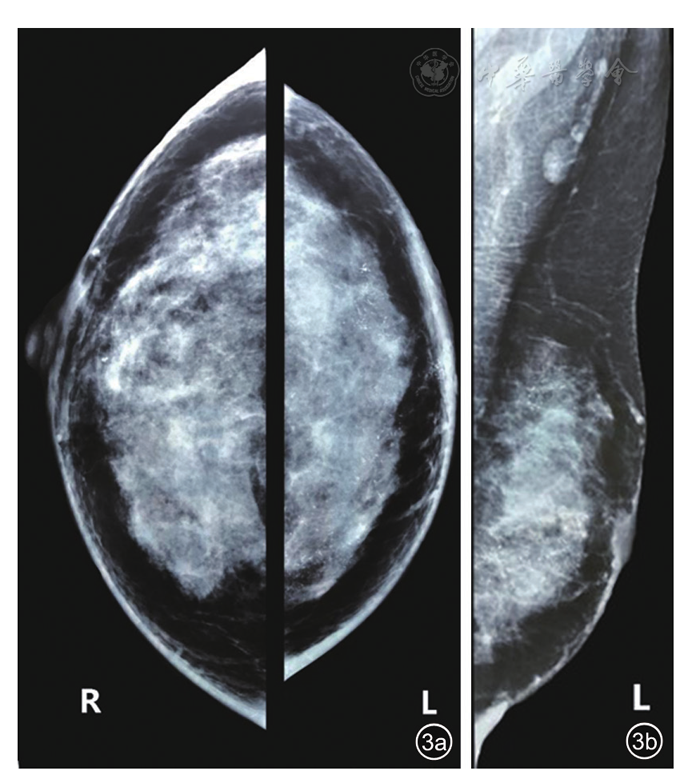

图3 乳腺钼靶图。图a双乳钼靶侧位片;图b左乳钼靶斜位片,左乳头未见明确显示,左乳晕区皮肤增厚,腺体内见多发点状钙化灶,呈分支状及短棒状改变:左侧腋窝淋巴结